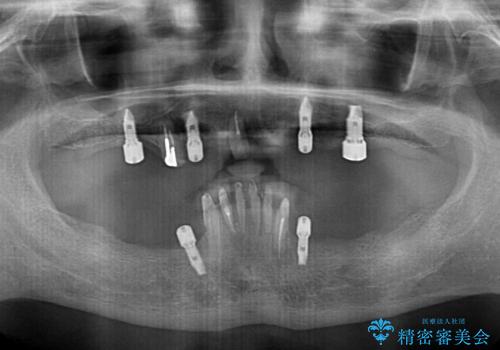

- どこで咬んでよいのか分からないとのことで来院された患者様です。

歯冠の崩壊した奥歯と、前歯の一部でした咬み合うことができず、入れ歯も試したものの、装着することができなかったようです。

全顎的にインプラント補綴を行うことも検討しましたが、費用面から、インプラントを土台とした入れ歯(インプラント・オーバーデンチャー)による補綴治療を行うこととしました。

入れ歯の固定源にはマグネットやロケーター、ボールアタッチメントなどがありますが、お住まいが遠方であることや、奥歯に力がかかりやすいことから、維持力が強く、メインテナンスが行いやすいロケーターを採用しました。